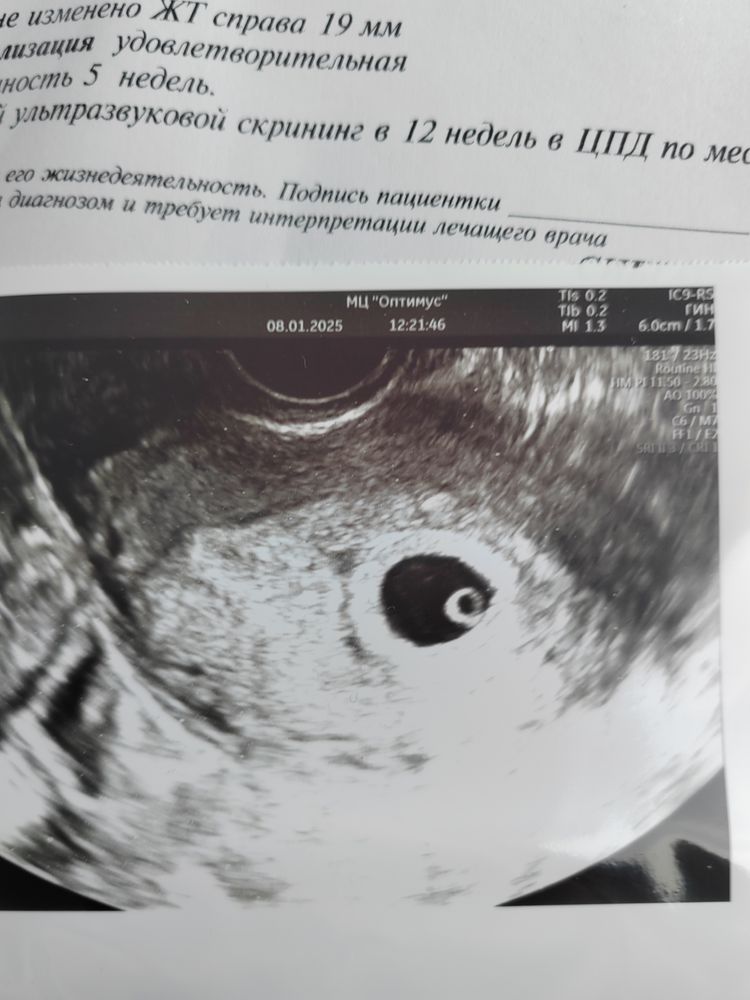

Делала тоже в 5 недель и 6 дней :-) тоже такой :-) только уже видно было пульсацию сердечка, врач звук не стала включать, сказала чтоб лишний раз не беспокоить :-) всё у вас нормально :-) Изображение

Как раз таки колечко и быть должно✅

У вас с боку видится что-то) на ту самую точечку похоже)

У вас там как будто видно с права запятую 😻